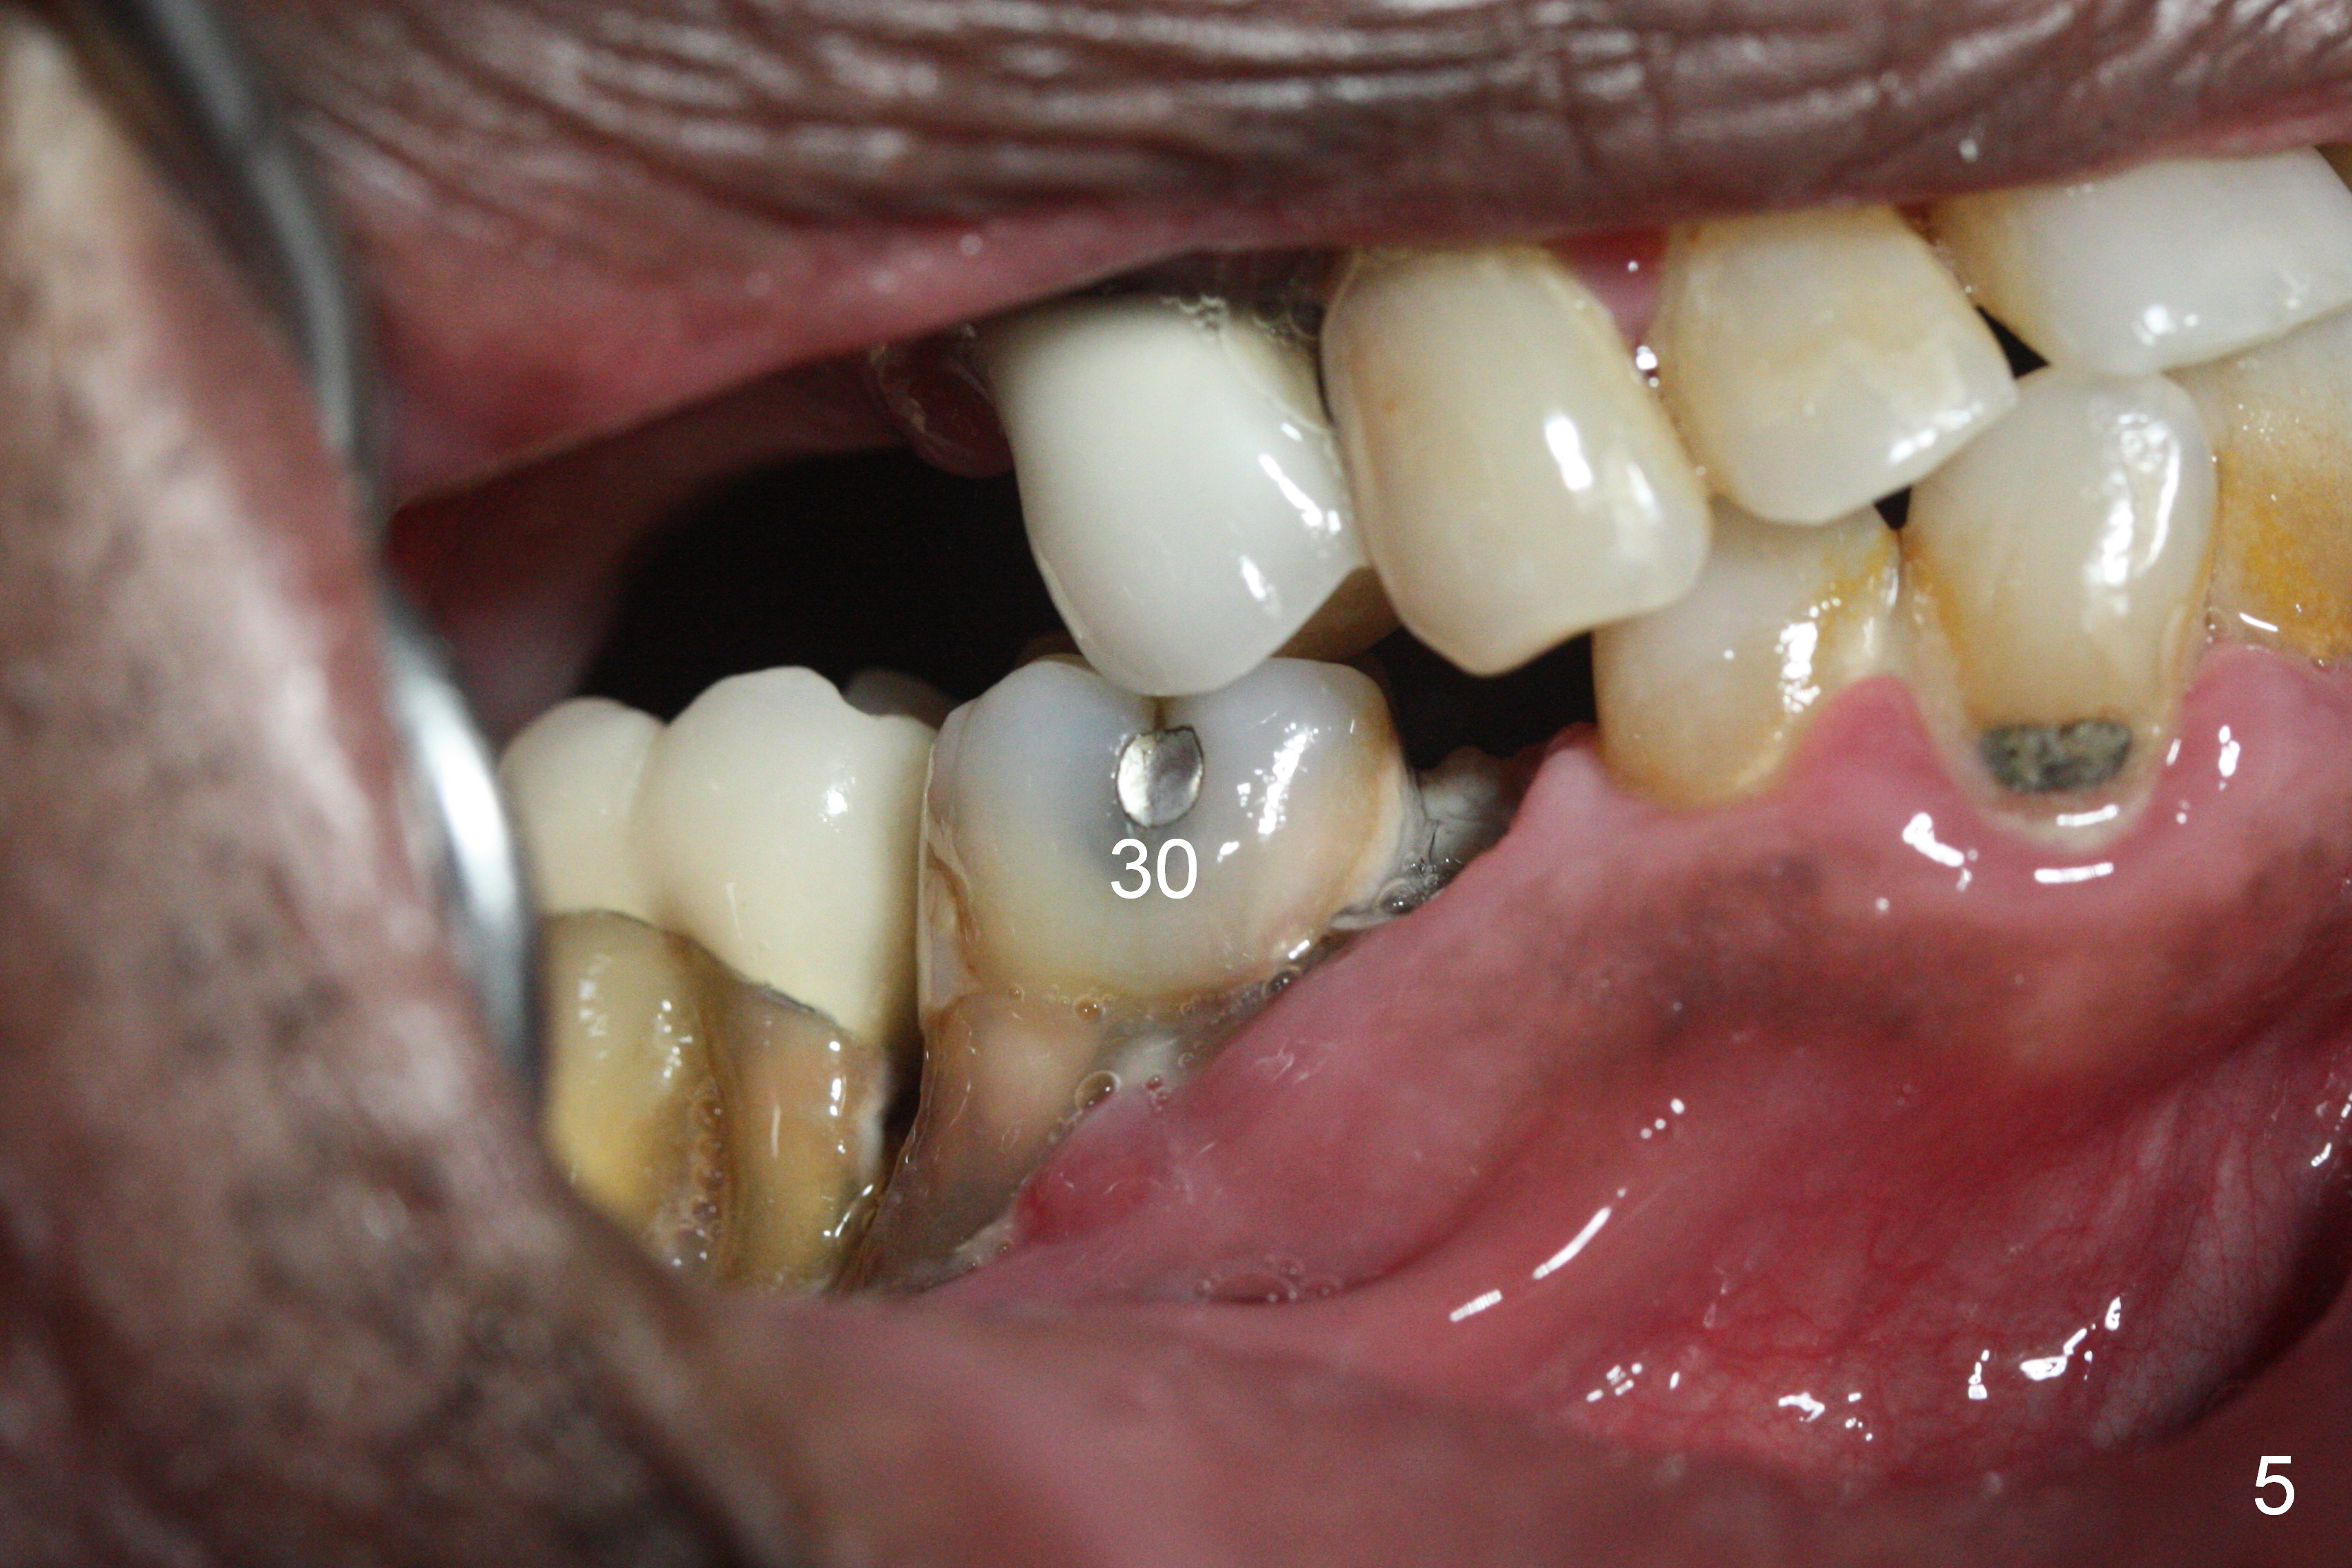

A 71-year-old man had poor dentition 4 years ago (Fig.1). Since then severe bone loss has occurred at the teeth #2 (Fig.2 *), 30 and 31 (Fig.3 *). An original plan is to place implants at #29 and 31 and fabricate a 3-unit bridge. Since the bone height at #31 is limited, primary stability may be questionable. It is advantageous to place 3 implants at #29-31. As the bone loss is severe and the sockets at #30 and 31 are long (Clindamycin), a fairly long portion of the implants at #30 and 31 will be not covered by the native bone (Fig.4 yellow line: 6-7 mm, bare) in spite of using 6 mm cuff (pink) of 7 mm abutments (brown). Use initial drill from DIO Sinus Master Kit with 5 mm stopper at #31 (green line), followed by insertion of a marked parallel pin. Use regular drills with stoppers of 10 and 8 mm at #29 and 30 (green line). Continue osteotomy at #31 with round drills (2.8 and 3.6 mm) with shorter stopper to avoid injury to the underlying Inferior Alveolar Canal (red dashed line). Pack allograft well around the implants at #30 and 31 before placing abutments to reduce periimplantitis and insert collagen plug around the abutments to prevent loss of the bone graft underneath. The last method to secure the bone graft is a retentive, splinted provisional.

It appears that the endo perio disease is more severe than 6 months ago (Fig.5,6). Prepare PRF and Extra Wide implants as well.